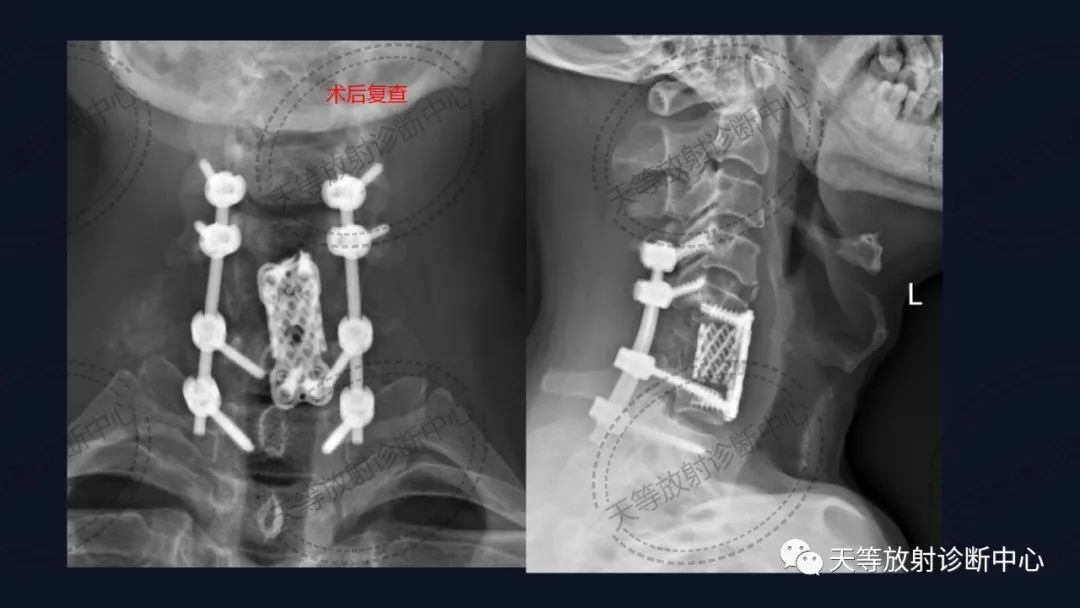

术后内固定支架